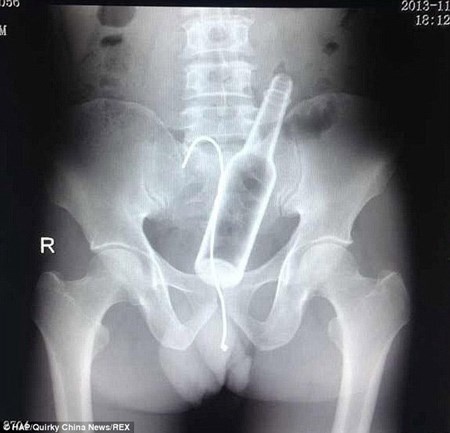

| Người đàn ông Trung Quốc đã lỡ nuốt cái chai vào bụng và trong cơn hoảng loạn ông lại nuốt thêm dây để "câu" cái chai ra ngoài. |